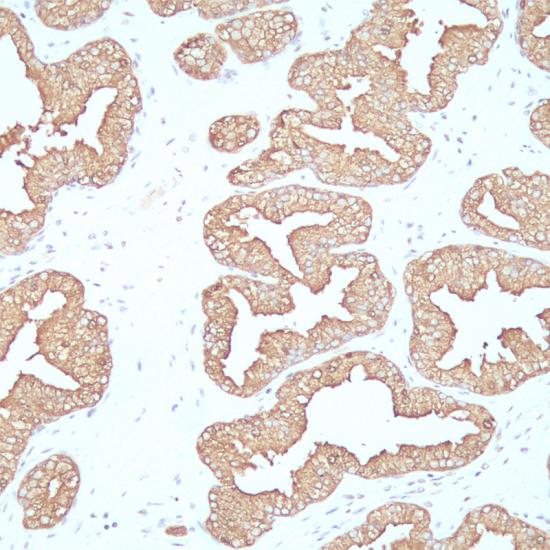

PSAP(前列腺特異性酸性磷酸酶)是由前列腺上皮細(xì)胞分泌的一種酸性磷酸酶的同工酶,在正常前列腺、增生的前列腺組織和前列腺癌中均表達(dá)PSAP。此抗體主要用于前列腺癌和轉(zhuǎn)移性前列腺癌的診斷。

• 陽性部位:

細(xì)胞漿

• 陽性對照:

前列腺癌